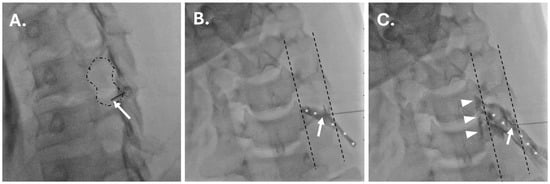

Safety of Perineural Lidocaine in Cervical Nerve Root Injections: A Retrospective Case–Control Study

by Kevin E. Salinas, Samir Ghandour, Jingyan Yue, Ronald W. Mercer and Zachary E. Stewart

Background/Objectives: Fluoroscopically guided cervical nerve root corticosteroid injections are used for the treatment and diagnosis of radicular pain. Including a local anesthetic with the injected corticosteroid may decrease the pain associated with the procedure and add immediate diagnostic value. However, little is known [...] Read more.

Background/Objectives: Fluoroscopically guided cervical nerve root corticosteroid injections are used for the treatment and diagnosis of radicular pain. Including a local anesthetic with the injected corticosteroid may decrease the pain associated with the procedure and add immediate diagnostic value. However, little is known about the safety of including a local anesthetic with a corticosteroid in these injections. Methods: A total of 299 consecutive cervical nerve root injections, performed between 2016 and 2024, were reviewed. Demographic and injection information (level/laterality and inclusion/exclusion of 1% preservative-free lidocaine with dexamethasone injectate) were documented. Charts were reviewed for major complications and increased pain post-procedure. Categorical data were compared between groups using Fisher’s exact test or Chi-square testing. Results: Injections were performed with 10 mg of dexamethasone only in 263 cases and with a mixture of 10 mg of dexamethasone and 1 mL of 1% lidocaine in 36 cases. There was no statistically significant difference in the incidence of major complications (p ≈ 1) or immediately increased pain post-procedure (p = 0.799). Conclusions: With proper technique, there is no evidence from this case–control study or in the available literature to suggest that including lidocaine with corticosteroid increases risks associated with cervical nerve root injections. However, serious adverse events are theoretically possible with injection of local anesthetic into a radicular artery, the vertebral artery, or subdural space. Given that such risks are not associated with the use of non-particulate steroids alone, large multi-institutional studies are needed to draw confident conclusions on the risks and benefits of the inclusion of local anesthetics with non-particulate corticosteroids for cervical transforaminal epidural steroid injection to inform clinical practice. Full article

Show Figures

Figure 1